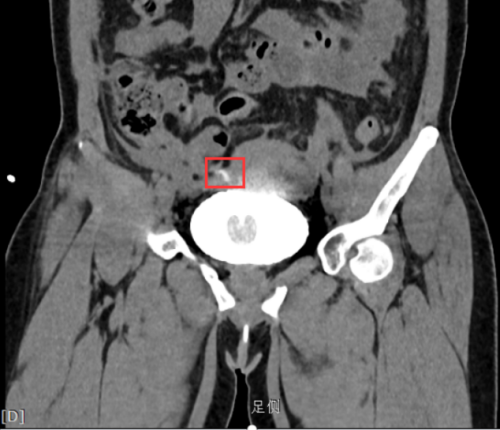

危急时刻,由泌尿外科、普外科和放射科组成的MDT团队迅速启动应急诊疗方案。放射科团队创新性地采用逆行性CT膀胱造影技术:通过尿道导管精准注入恒温造影剂,结合256层螺旋CT动态扫描,成功捕捉到膀胱顶壁一处细微的造影剂外渗征象。三维重建图像清晰显示病灶位于膀胱穹顶区,呈现特征性的“星芒状”渗漏模式。

膀胱穹顶区可见“星芒状”(红框内)渗漏

基于放射科提供的精准影像定位,当晚泌尿外科与普外科团队联合为李女士实施急诊手术。术中所见与影像诊断完全吻合:膀胱顶壁存在直径约0.5cm的陈旧性憩室破裂口,周围被大网膜包裹形成假性闭合。手术团队顺利完成膀胱修补和腹腔脓液清除,术后病理证实为慢性炎症导致的膀胱壁薄弱破裂。